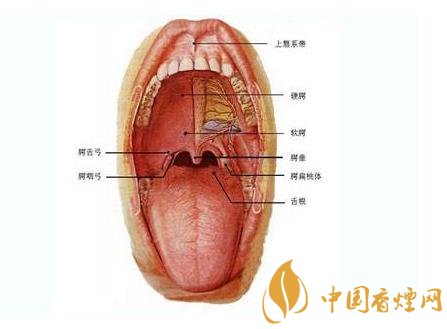

吸烟也是口腔癌的最主要的因素。口腔癌前病变的白斑,绝大多数是由吸烟引起的,只要戒烟,大部分的口腔粘膜白病去自动消失,产生口腔癌症的可能性就会大大降低。

吸烟是口臭的重要来源之一吸烟的人多半有一股令人讨厌的口臭。有一位著名的社会牙医学家孙迪拉姆,他的戒烟经验就是为了消除口腔的烟臭。因为他的小女儿最讨厌他的口腔有烟臭。最害怕和她爸爸亲吻,他甚感伤心,为此他就下决心戒了烟。

吸烟往往使牙齿染上黑色特别是下前牙的舌侧牙颈部,刷牙也不易刷掉,当张嘴一笑,就要露出黑兮兮的牙齿,尤其是在社交场合这种尴尬局面很难挽回吸烟者给初次见面者留下难以忘掉的不良影响。